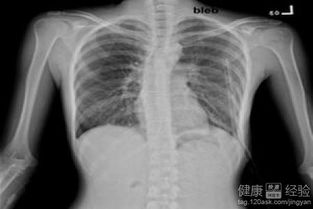

气胸是一种肺部疾病,简单来说就是气体跑到了不该去的地方。正常情况下,我们的肺和胸壁之间有一个密闭的空间,当某些原因导致肺泡破裂时,气体就会进入这个空间,造成压力升高,从而压迫肺部,影响呼吸功能。这种情况如果不及时处理,可能会危及生命。

住院期间,小李接受了胸腔穿刺抽气治疗,医生通过一根细长的针管将胸腔内的气体抽出,缓解了症状。随后又进行了几天的观察和药物治疗,确保病情稳定后才允许出院。